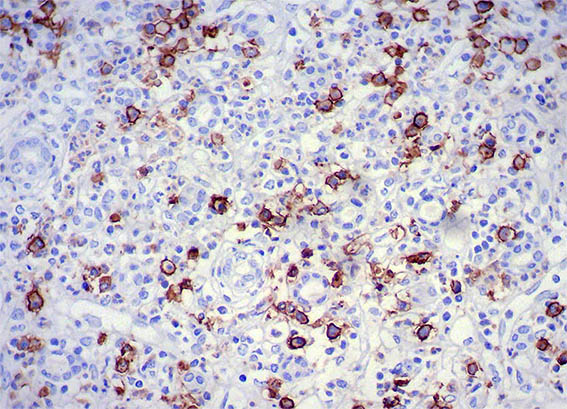

Figura 11. Inmunohistoquímica para IgG4, X200.